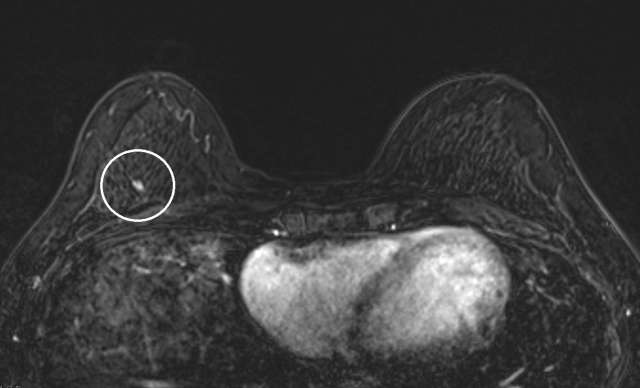

The mammographic appearance of ADH is usually that of grouped or regional calcifications, most often of the amorphous or coarse heterogeneous subtype. ADH can also be less commonly present as a mass or focal asymmetry on screening mammograms. As calcifications are the most common presentation of ADH on screening mammograms, and as ultrasound suboptimally evaluates areas of calcification, ADH is less often seen on ultrasound examinations. However, the most common sonographic feature of lesions demonstrating ADH on ultrasound-guided biopsies includes a hypoechoic, microlobulated mass without acoustic transmission or shadowing. The most common appearance of ADH on breast MRI is nonmass enhancement in a focal, linear, segmental, or regional distribution. The second-most common appearance is that of an enhancing mass.